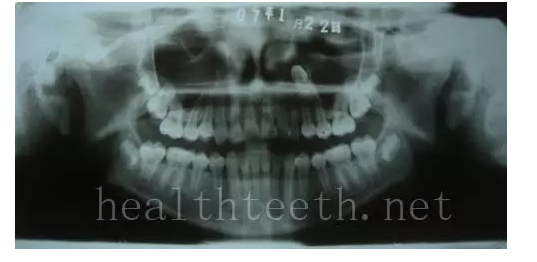

左上乳3滯留,恒3未見萌出,曲面斷層片顯示牙齒埋伏

通過CT片確定埋伏牙齒具體的位置,顯示距離左側(cè)上頜竇很近,偏唇側(cè),這為手術(shù)定位提供了方便

手術(shù)中切斷、完整拔出,未損傷上頜竇